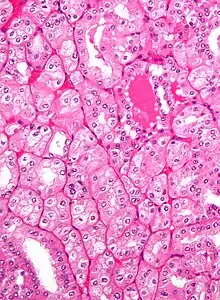

|

Clear Cell Renal Cell Carcinoma (CCRCC) ![]() Generally the cells have a clear cytoplasm, are surrounded by a distinct cell membrane and contain round and uniform nuclei. |

60–70% |